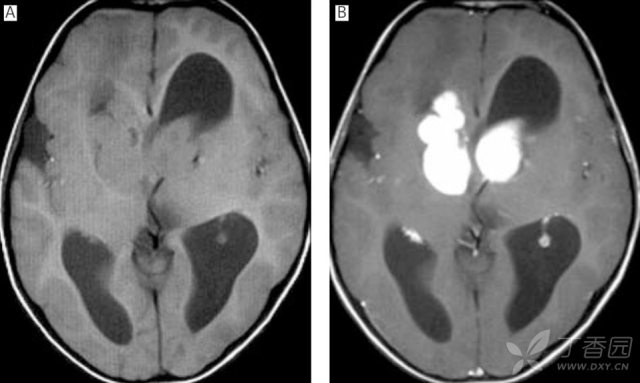

图 1:31 岁难治性癫痫伴右侧海马硬化男性患者;A:T2WI;B:FLAIR;可见右侧海马高信号伴萎缩

海马硬化的典型 MRI 特征为海马体积缩小,T2/FLAIR 信号增高和海马内部结构模糊,可伴有同侧的侧脑室颞角扩大、颞叶萎缩等。在颞叶癫痫伴海马硬化的患者 MRI 上常可出现同侧颞极的灰白质异常(「颞极模糊」),在 MRI 上表现为灰质与白质分界不清及 T2 高信号。需与单纯的海马萎缩、海马旋转不良相鉴别。海马旋转不良指单侧的海马旋转不完全,其形态异常,但内部结构混乱,但海马体积和信号正常。